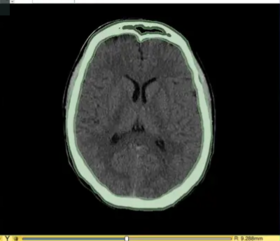

该图展示了如何使用3D Slicer来对CT和MR数据中的头骨条纹进行分割。